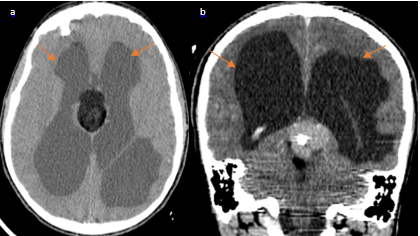

A 12-year-old male patient with a 2 months history of intermittent headaches, presented with acute onset nausea, headache, and projectile vomiting while sitting at school. After seeking medical attention, he was found to be neurologically intact on physical exam. CT scan of the head was performed and demonstrated a mixed density mass in the pineal region with central calcifications, and soft tissue components (Figure 1). Hypodense lesions were seen in the lateral ventricles, third ventricle, and quadrigeminal cistern. The lesions in the lateral ventricles demonstrated hypo attenuations as low as -93 Hounsfield Units, consistent with fat with frontal horn level (Figure 2 & Figure 3). Ventriculomegaly was also evident, due to the obstruction of the aqueduct of Sylvius.

Figure 2 Cerebral CT scan in axial (a) and sagittal reconstruction (b) showing hypodense lesions in the lateral ventricles consistent with fat content forming a supernatant lipid layer floating on the CSF in the superior portions of both lateral ventricles, very suggestive of intra-ventricular rupture..